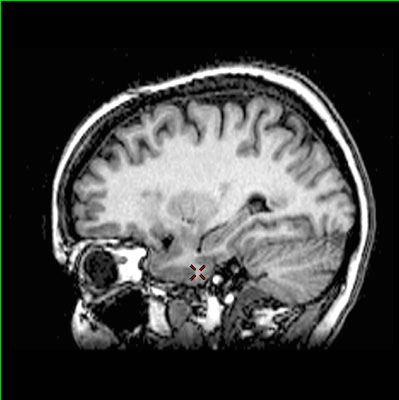

Localisation du gyrus fusiforme

L'image IRM en coupe permet de localiser le gyrus fusiforme dont la lésion est mise en cause dans la prosopagnosie.